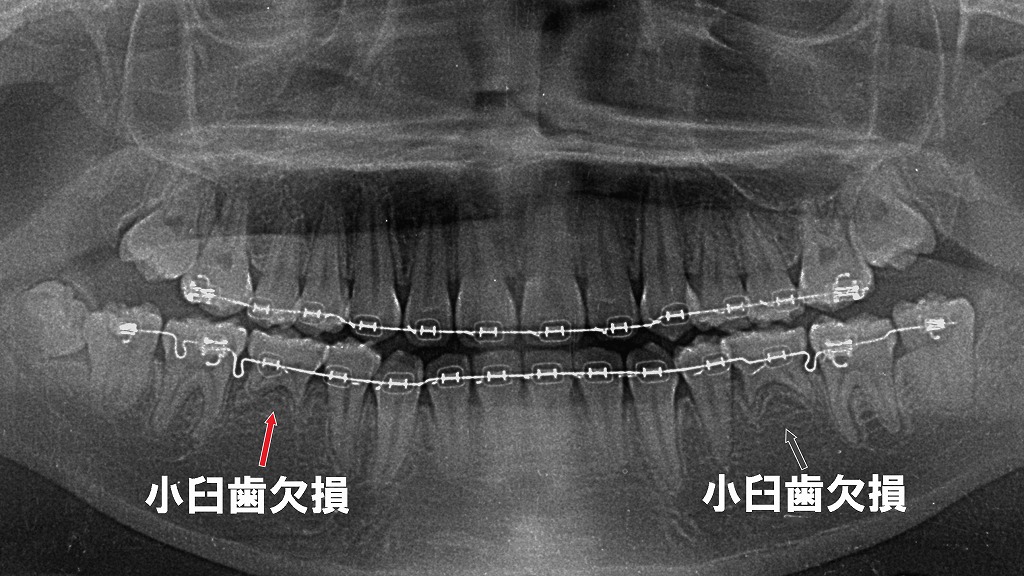

本症例では、左右の4番が先天欠損しており、下顎前歯部に明確な空隙が形成されています。正面観・咬合面観・側方面観から、欠損による特徴的な歯列変化が分かりやすく確認できます。

下顎の左右第一小臼歯(4番)が先天欠損(上顎は正常)しており、その影響で下顎前歯部にすき間(空隙歯列)が生じている症例です。欠損により歯列の連続性が途切れ、噛み合わせや前歯の並びに特徴的な変化が見られます。

左右の第二小臼歯が先天欠損しているため、乳歯Eにブラケットを装着し、咬合と歯列のバランスを整える矯正治療を行っています。乳歯を歯列の一部として活用しながら、スペース管理と乳歯Eが脱落した場合の咬合を考慮した治療計画が必要になります。